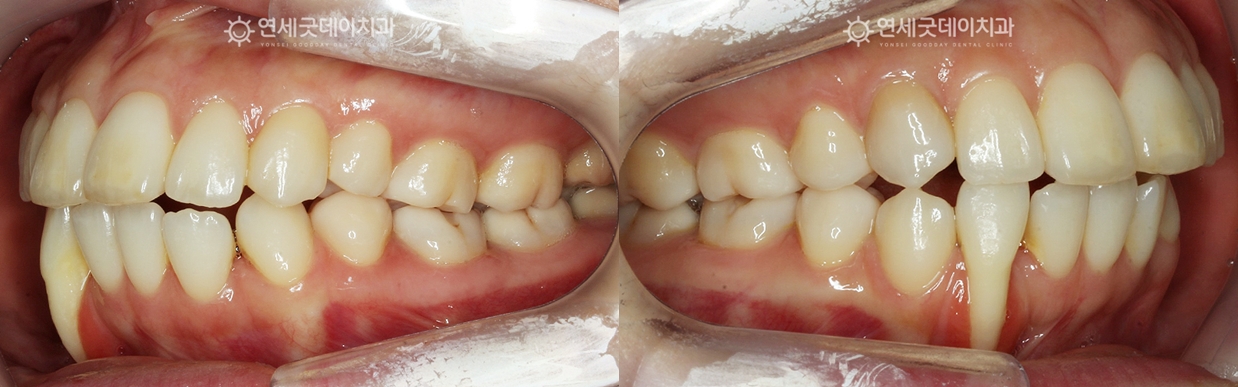

▲ 치료 중 (촬영시기 : 2025년 3월)

아랫니 부분교정으로 치아 배열을 개선하는 과정입니다.

치아가 잘못된 위치에서 잇몸뼈 안으로 올바르게 위치하면서